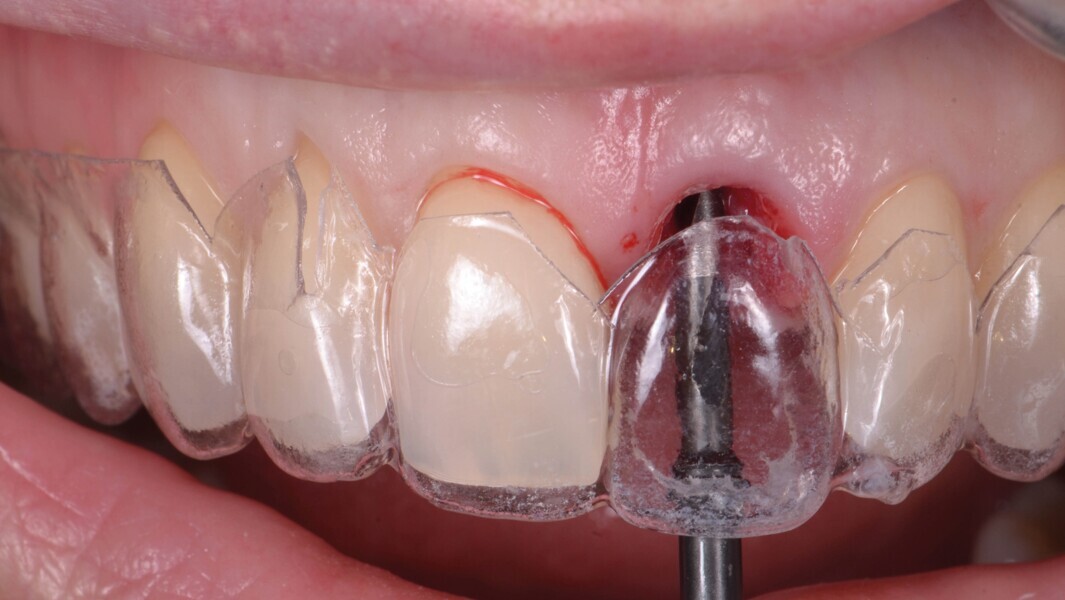

Fig. 12a : Un second guide fabriqué sur la base du wax-up diagnostique. La morphologie de la dent et le profil d’émergence ont été reproduits et servent de référence pour le positionnement de l’implant. (a et b).

Fig. 12b : Un second guide fabriqué sur la base du wax-up diagnostique. La morphologie de la dent et le profil d’émergence ont été reproduits et servent de référence pour le positionnement de l’implant. (a et b).

Aucune concavité vestibulaire n’est présente et le contour de crête est correct. À ce stade, l’objectif principal est atteint : la cicatrisation post-extractionnelle est atteinte. La priorité passe des lors a la préservation de l’architecture des tissus lors de la phase implantaire. À cet effet, un protocole combinant l’élévation d’un lambeau de petite étendue et une chirurgie guidée avec forage pilote est alors exécuté (Fig . 10).

Un implant (Aadva Regular, GC Tech), avec une connexion conique interne associée au concept du platform switching, est mis en place (Figs. 11–12). La dent provisoire est ensuite collée à nouveau aux dents adjacentes